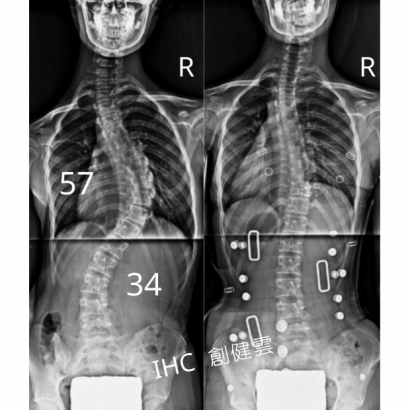

15歲脊椎側彎男孩

胸彎40度